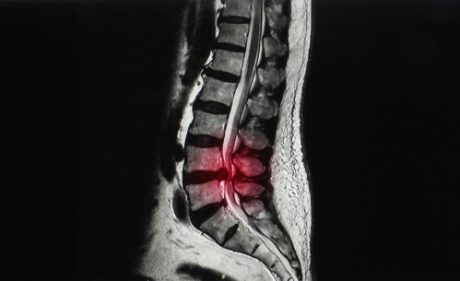

After being given adequate pain relief, an MRI scan was carried out, and KH was sent to Ipswich Hospital. He wasn’t told what was going on, only that he needed emergency surgery. When he arrived at Ipswich Hospital, it was revealed that a disc in his lumbar spine had ruptured. The disc’s material had spread onto the cauda equina nerves, causing severe compression. KH underwent emergency surgery for decompression.